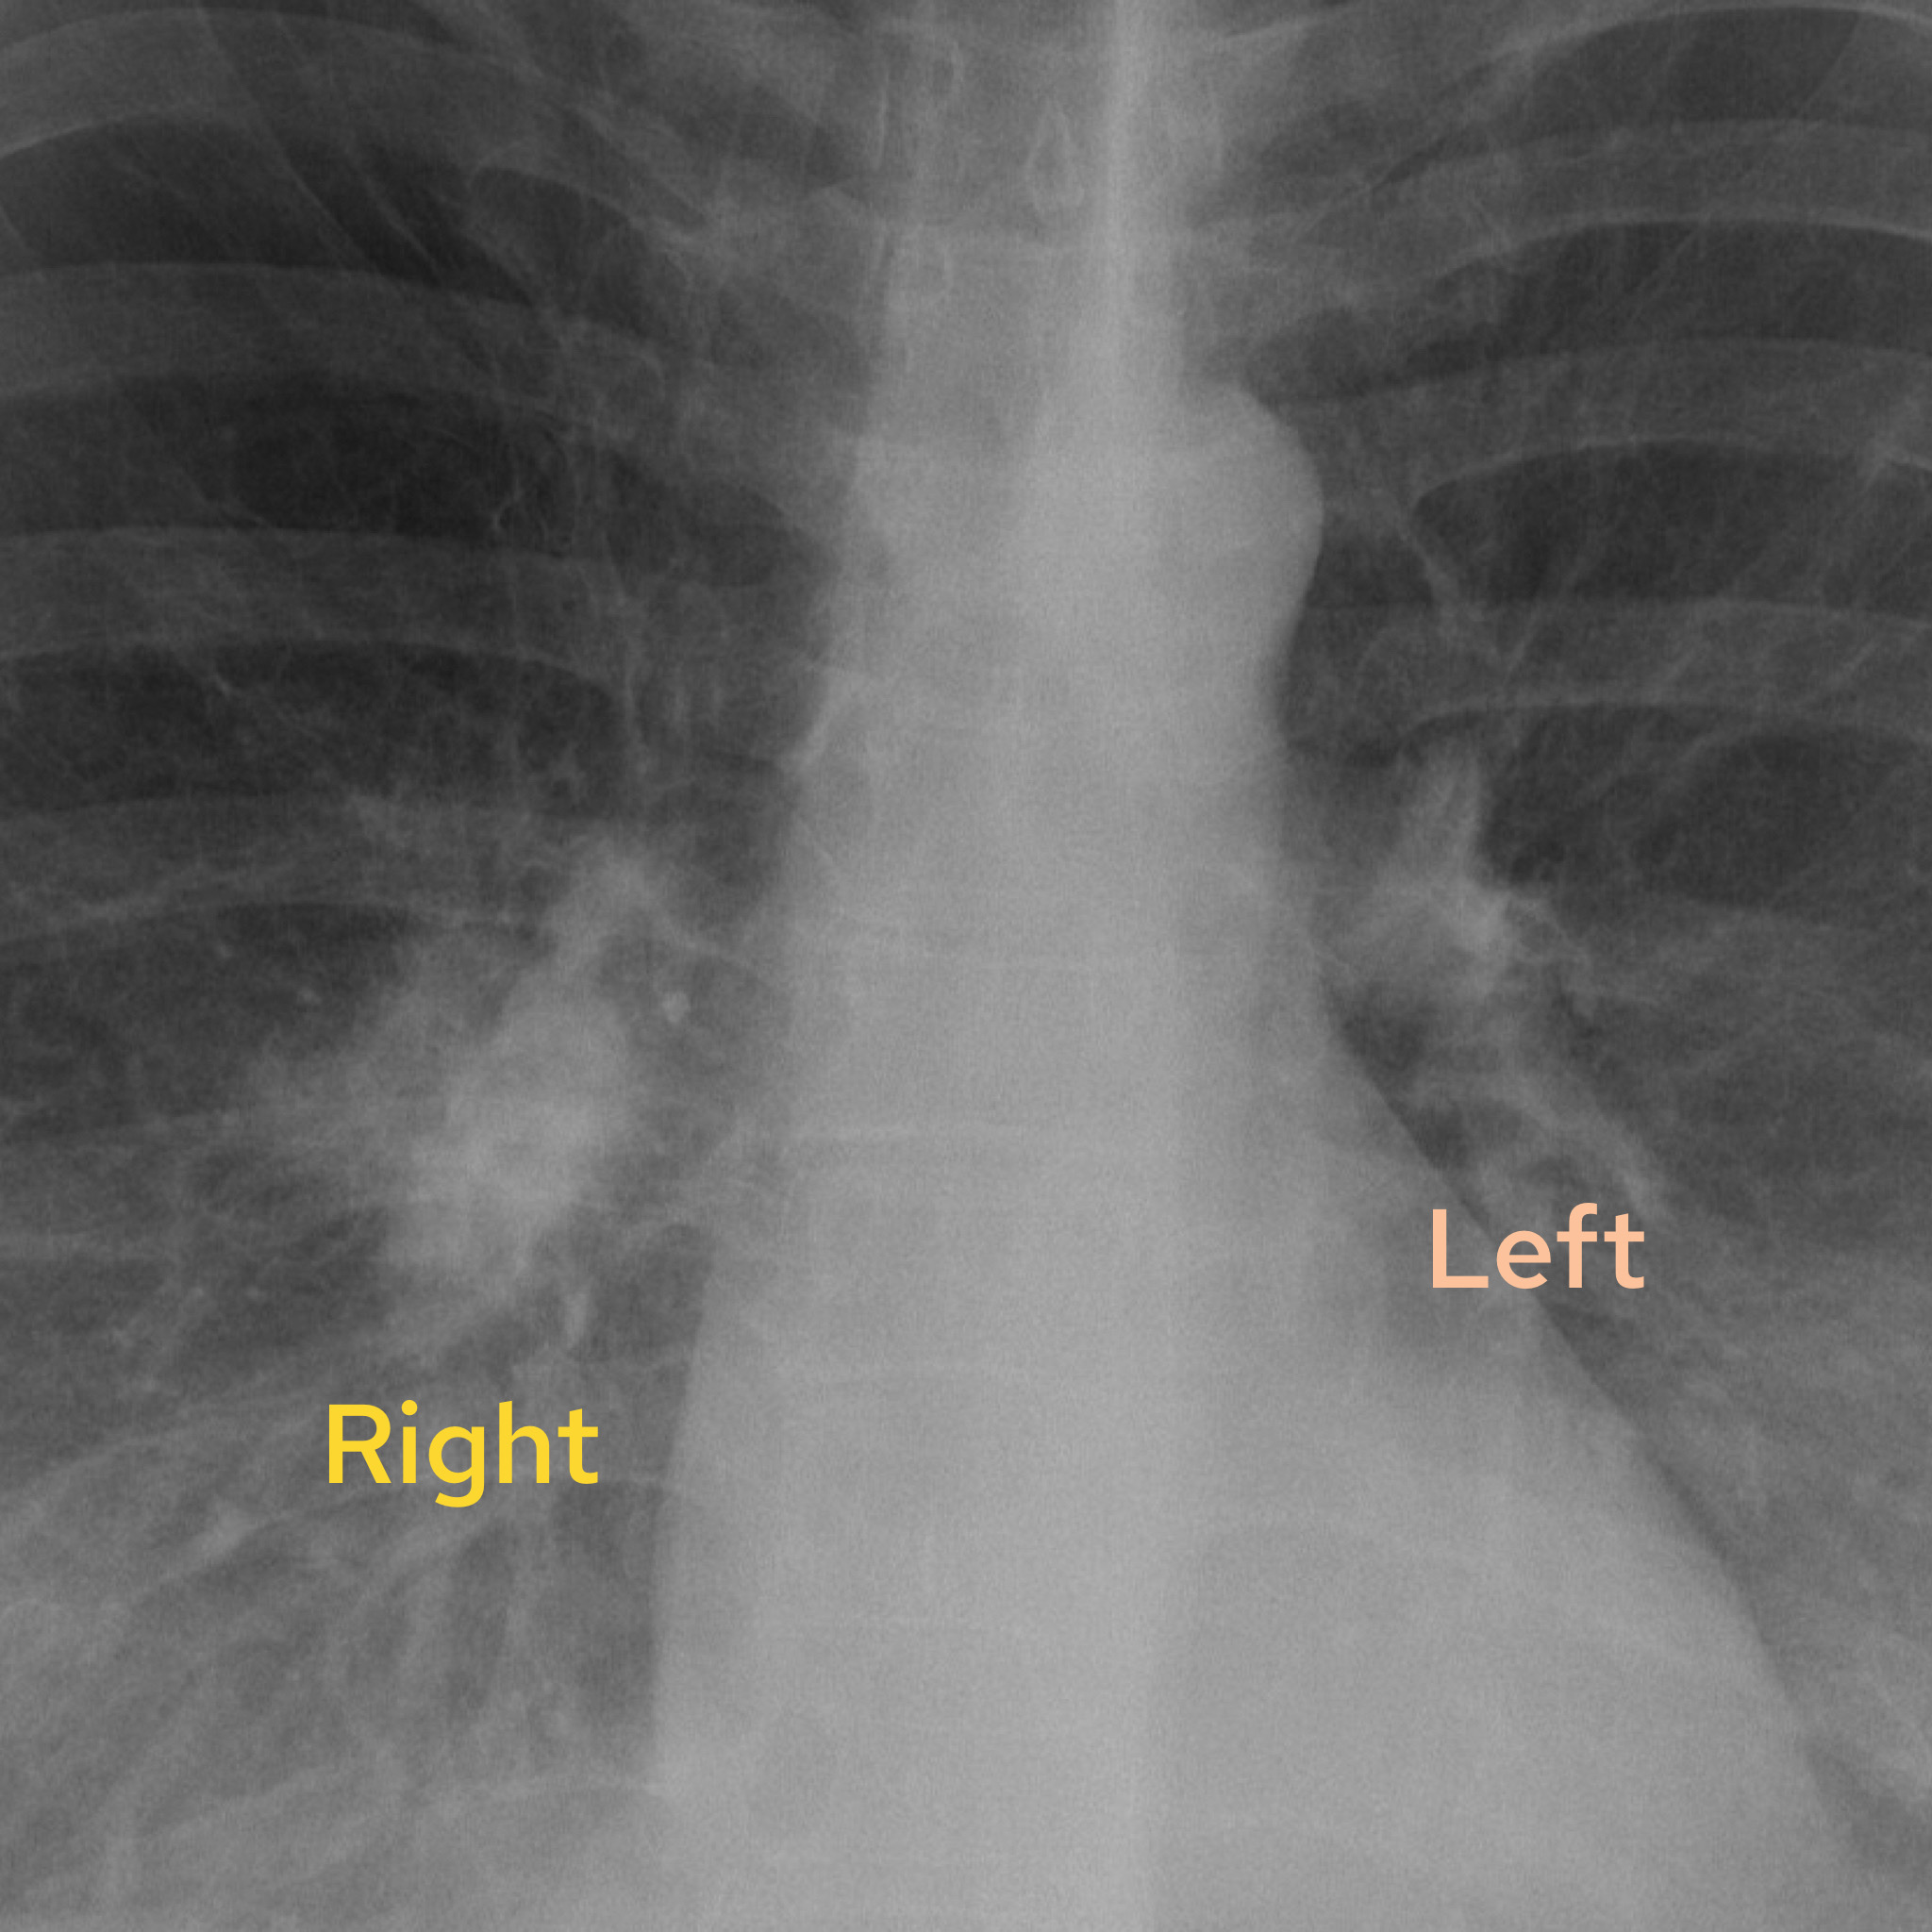

Case 1

A female in their 60s presents with unremitting cough on a background of weight loss. Have a look at the chest X-Ray below:

What is the most likely diagnosis? Choose from one of the following: